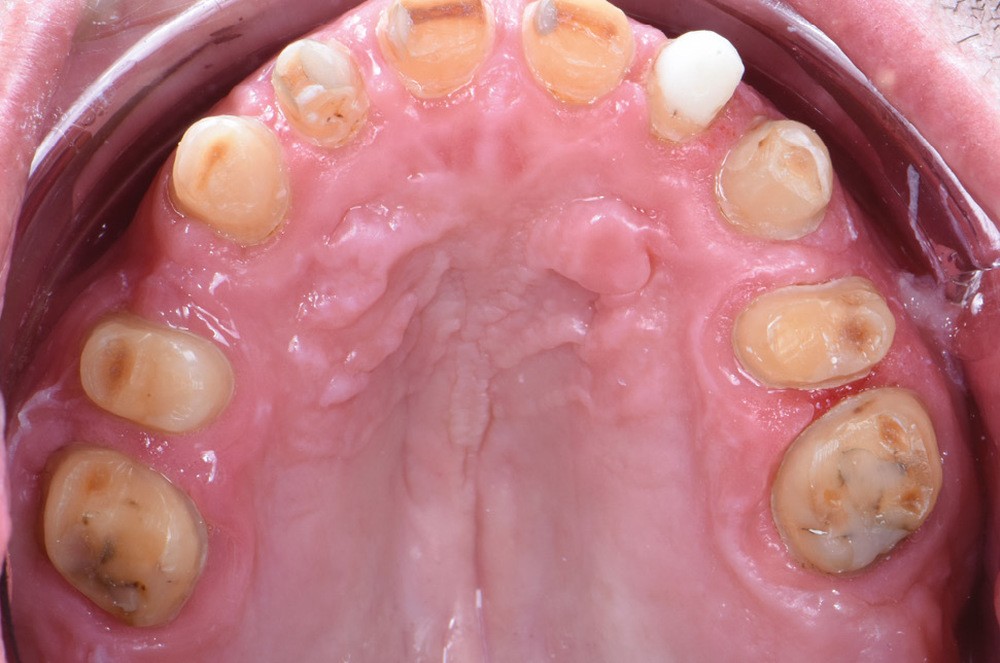

Au vu du contexte para-fonctionnel et de l’étendue de la perte tissulaire, des coiffes périphériques minimalement invasives ont été choisies afin de restaurer l’esthétique et la fonction. Actuellement, aucun consensus n’est fait sur le choix du matériau d’infrastructure à privilégier. Les matériaux hybrides usinables présentent des propriétés mécaniques, physiques et biologiques intéressantes en contexte d’usure sévère (e.g., module d’élasticité, résistance à la propagation de fêlures, facilité de réintervention). Une réhabilitation globale avec remontée de dimension verticale d’occlusion (DVO) par l’intermédiaire de coiffes composites renforcés en nano-céramiques est décrite.